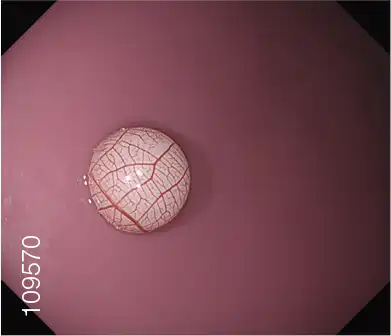

The GIF-XZ1200 is a state-of-the-art magnifying gastroscope that enables visualization of the finest details of suspicious lesions with up to 125x*1 magnification. This advanced optical performance is boosted by NBI (Narrow Band Imaging) capability for even more discriminating observation, supporting increased diagnostic accuracy and confidence.

White Light Image Optical 125x magnification with NBI